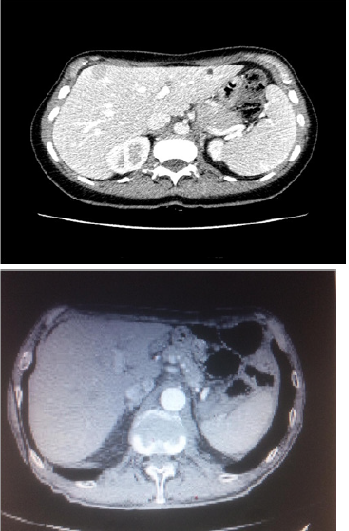

On July 2018 patient began with 2 weeks of no responsive cough to symptomatic therapy. Due to persistent cough she underwent to a chest X ray, which showed a suspected opacity area in the right upper lobe. Due to the imaging deriving from chest X Ray, she received a chest CT scan that showed a 5 cm solid lung lesion in the right upper lobe. Enlarging the field the CT scan revealed a 2 cm solid lesion in the V liver segment too. Due to radiological finding arising from CT scan, and in order to give the patient the correct staging, on 25th of July patient underwent to a 18 FDG Pet Scan that revealed an increased level of standard uptake values (SUV) in the right lung upper lobe (SUV 35), in spleen, left iliac bone, fifth liver segment and Dorsal vertebra (D3).

The treatment went on for 3 months with good tolerance and no relevant toxicities in patient reported outcomes. Not hematologic toxicities were described too. After only 2-3 weeks of treatment patient revealed an impressive cough improvement maintaining an optimal quality of life. The 18 FDG Pet- CT scan performed in January 2019, after three months of treatment showed a complete radiological response on spleen, left iliac bone, liver and D3, and a partial response (RECIST criteria) on pulmonary lesion. Cough completely disappeared and no toxicities appeared during the first three months treatment with Alectinib full dose.

Figure 1 & 2. Hepatic lesion in 07.18 TC scan in complete response in 01.19 TC scan